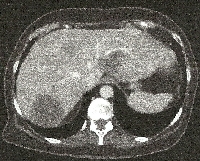

Πρόκειται για γυναίκα ασθενή 63 ετών που, στα πλαίσια διερεύνησης άτυπων κοιλιακών ενοχλημάτων και τρανσαμινασαιμίας, διαπιστώθηκε ότι έπασχε από αποφρακτικό αδενοκαρκίνωμα του σιγμοειδούς με σύγχρονες πολλαπλές (type II) ηπατικές μεταστάσεις (εικόνες 1 & 2). Ο περαιτέρω έλεγχος σταδιοποίησης ήταν αρνητικός για εξωηπατικές μεταστάσεις. Υιοθετήθηκε η κλασσική προσέγγιση (classic approach) αντιμετώπισης της νόσου με βάση το ακόλουθο πλάνο: α) ενδοσκοπική μεταλλική ενδοπρόθεση (stent) σιγμοειδούς, β) εισαγωγική χημειοθεραπεία, γ) κολεκτομή (εικόνα 3) και εκτομή των ηπατικών τμημάτων 2 & 4a (εικόνα 4), δ) διάμεση χημειοθεραπεία, ε) δεξιά ηπατεκτομή (εικόνες 5 & 6) και στ) μετεγχειρητική χημειοθεραπεία. Η ασθενής εξακολουθεί να παραμένει ελεύθερη νόσου στις τακτικές απεικονίσεις παρακολούθησης.